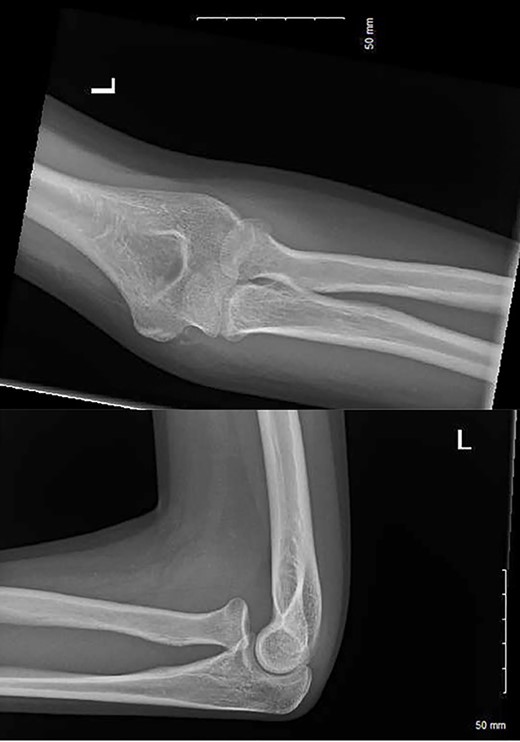

After 1 month, the patient arranged a face-to-face follow-up due to ongoing pain, extensive haematoma and limited range of movement (Fig. 2). On assessment by an orthopaedic consultant, the range of movement was limited to 30–100°, supination to 50° and full pronation. Repeat radiographs demonstrated the radial head had now dislocated anteriorly, suggestive of annular ligament rupture (Fig. 3).

The injury pattern in our case (ipsilateral radial neck fracture with annular ligament rupture) is rare—most traumatic radial head dislocations occur as part of a Monteggia fracture pattern. Despite its rarity, orthopaedic examination would have immediately raised concern for significant ligamentous injury given the extensive haematoma (Fig. 2) and limitation in the range of movement evident. VFC advice leaflets for all elbow injuries must underscore the need for face-to-face consultation if significant bruising or limitation in the range of movement persists beyond 1 week post-injury.